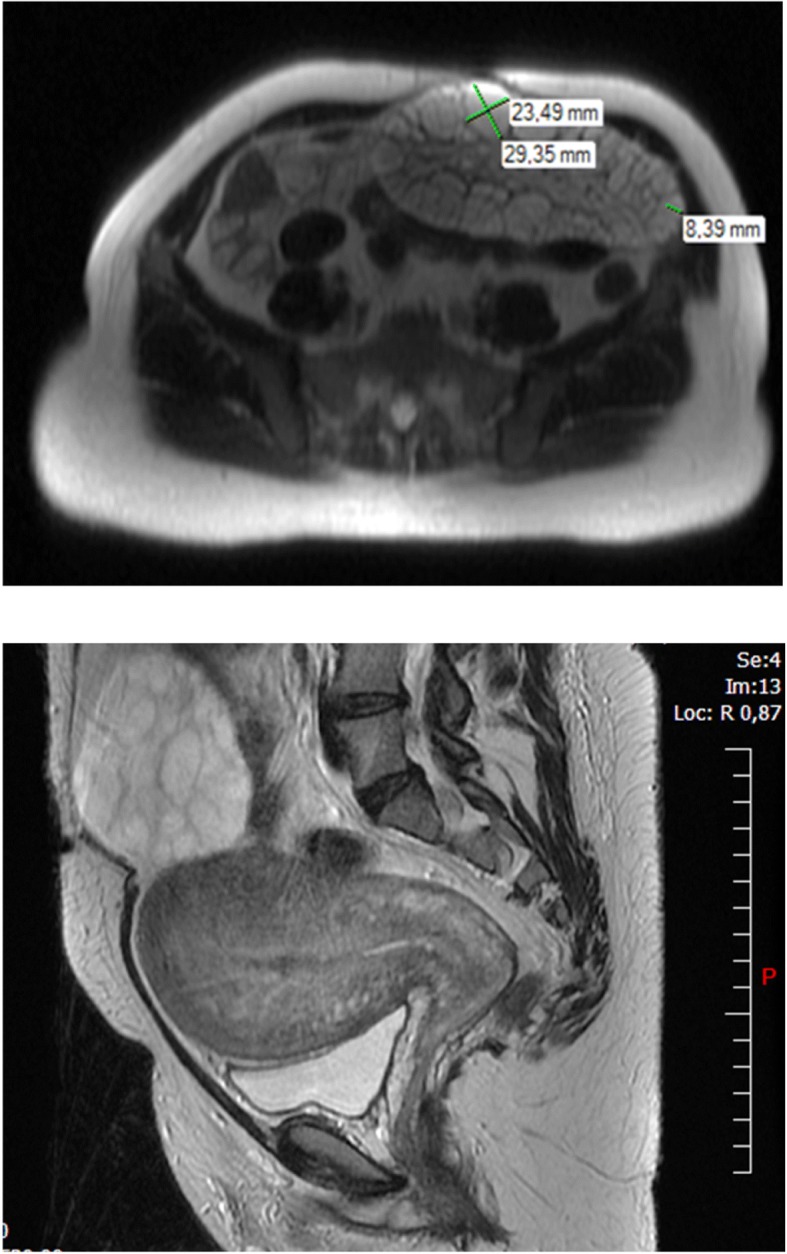

A pelvic ultrasound (U/S), performed in the first trimester of the 4th pregnancy to exclude ovarian causes of hyperandrogenism (luteoma, luteinic cyst or malignant causes), described the single left ovary with an area of 9,9 cm2 and multiple microfollicles. At the same time, a Pelvic Magnetic Resonance Imaging (MRI) confirmed the polycystic ovarian pattern. In the immediate postpartum, another U/S described the polycystic aspect of the left ovary, that was a larger and an anechogenic cyst of 3.5 cm diameter (Fig. 1).

Fig. 1.

U/S of the left ovary in the immediate postpartum (Case 1)

A second MRI was performed 1 month postpartum because of pelvic pain, suggesting a subtotal ovarian torsion (Fig. 2a and b). The MRI described an enlarged left ovary of 16.5 × 8.2 × 10 cm, a polycystic aspect and an anechogenic cyst up to 3 cm. No detectable solid mass was observed. The ovary was twisted with a lack of vascularization within some parts of parenchyma. The MRI was non-contributive for this area. The clitoromegaly and the deep voice remained but the patient was lost to follow-up.

Fig. 2.

Pelvic MRI performed one month postpartum, left ovary (Case 1)